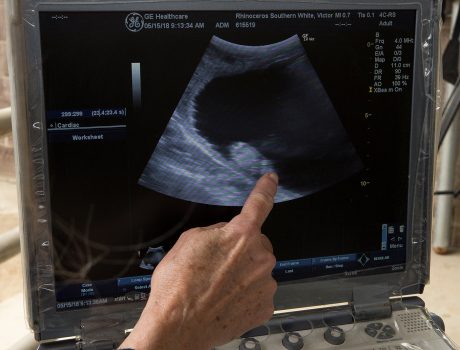

Conservationists Hope to Save the Species through International Breeding Program The San Diego Zoo has …